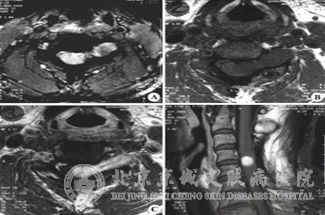

2、椎管内肿瘤:脊髓平面都可以发生单个或多个神经纤维瘤、脊膜瘤,能够合并脊柱畸形、脊髓膨胀出去和脊髓空洞症;